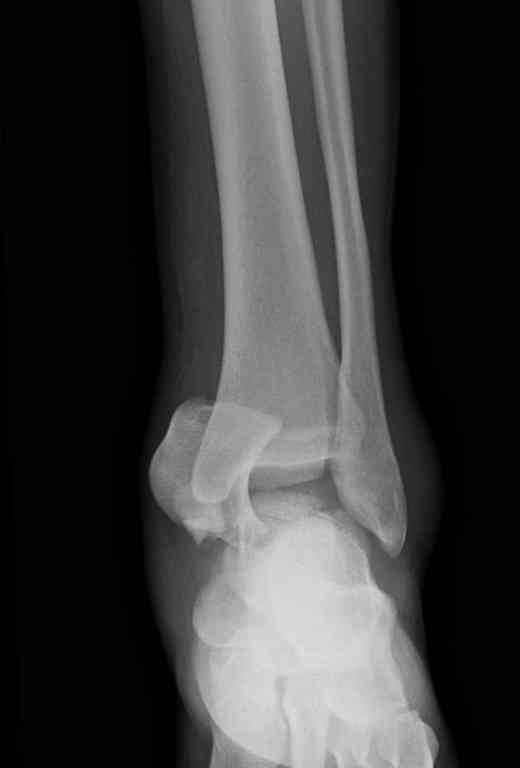

Прошу коллег помочь советом.3 дня назад поступила пациентка 23 года с переломом шейки ладьевидной справа, переломом лодыжек и заднего края б/берцовой кости со смещением и подвывихом кзади, переломом внутреннего мыщелка правого бедра без смещения. Дежурными хирургами проведена репозиция в левом г/ст суставе успешная, попытка репозиции таранной кости ухудшило положение отломков. Планируем провести повторную репозицию и фиксацию винтами. 1. Закрытая репозиция рентгенконтоль интраоперационный (аппарат Арман) ификсация из заднее-наружного доступа. 2. При неудачной закрытой репозиции переходим на открытое вправление двумя доступами медиальным и латеральным "по ходу оси таранной кости" и через дополнительный задний доступ вводим винты кортикальные 4,5 мм или 3,5 мм 3. после открытой репозиции фиксация двумя винтами через боковые доступы погружая их под суставную поверхность Сергей Зырянов ЦРБ Новосибирская область

Переломовывих тарана с повреждением медиальной стороны. Через 4 часа после поступления проведена репозиция и фиксация тарана после Irrigation&Debridment. Частичное несращение медиальной лодыжки не беспокоит, вернулся к активному образу жизни. Полная нагрузка разрешена через 11 недель. Финальные снимки через 11 месяцев.